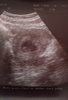

Cześć Cześć dziewczyny. U mnie wg USG 7 t6d serduszka nie widziałam ale sprzęt pozostawia sporo do życzeniano i usg przez brzuch

grunt że fasolka jest

14,6mmZobacz załącznik 892707